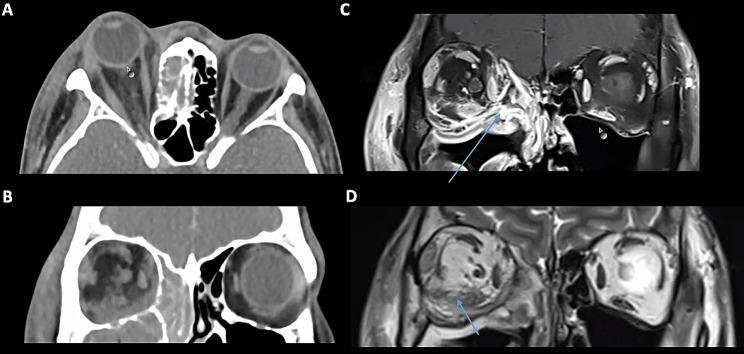

Four patients with odontogenic orbital cellulitis were identified for inclusion. There was an equal proportion of men and women with a mean age of 43 years (range 25-56 years). All patients presented with an orbital compartment syndrome, with visual acuity of counting fingers (n = 1, 25%), hand movements (n = 1, 25%) and no perception of light (n = 2, 50%). The organisms implicated were Streptococcus milleri (n = 3, 75%) and Streptococcus constellatus (n = 1, 25%). MRI findings showed a subperiosteal abscess was present in all cases, which was characterised radiologically as a T1-hyperintense, T2 minimally hyperintense collection with restricted diffusion and a low apparent diffusion coefficient signal. Final visual acuity ranged from 6/6 to no light perception. One patient required an orbital exenteration due to extensive necrosis with sepsis and systemic deterioration.

确定纳入4例牙源性眶蜂窝织炎患者。男女比例相等,平均年龄43岁(范围25 - 56岁)。所有患者均出现眶间隔综合征,视力分别为指数(n = 1,25%)、手动(n = 1,25%)和无光感(n = 2,50%)。涉及的微生物为米勒链球菌(n = 3,75%)和星座链球菌(n = 1,25%)。MRI表现显示所有病例均存在骨膜下脓肿,其影像学特征为T1高信号、T2轻度高信号,弥散受限,表观扩散系数信号低。最终视力范围从6/6到无光感。1例患者因广泛坏死伴脓毒症和全身状况恶化而需要进行眶内容摘除术。